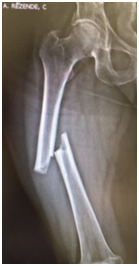

We report a case of bilateral femoral fracture in a patient after 7 years of treatment with alendronate at a dose of 70 mg weekly. The patient was a 67 y.o. female with no history of any comorbidity such as diabetes, alcohol abuse, smoking, chronic use of glucocorticoids or others. She fell from her own height in March 2014, resulting in a transverse femoral shaft fracture of the left femur (Figure 1A), treated with a blocked anterograde intramedullary nail (Figure 1B & 1C). In June 2016, she suffered a contralateral short oblique femoral fracture with no history of direct trauma, presumably with a torsional mechanism - rotation around the body axis (Figure 2A). The treatment of choice was also a blocked anterograde intramedullary nail (Figures 2B & 2C). We can observe in Figures 1 & 2 the absence of compromised trabecular bone or thinning of cortical bone, corroborating the probable pathophysiology behind bisphosphonate-associated fractures - decreased bone remodelling - and not osteopenia/osteoporosis.

Figure 2A Right femoral anteroposterior radiograph – Simple short oblique tract fracture with cortical thickening. 2B & 2C Postoperative radiography – anterograde blocked nail right femur.